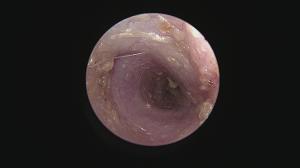

今回アップした動画は慢性外耳炎の中でも管理が困難な「耳垢腺過形成」による症例への治療動画になります

このような症例は管理が困難なため「全耳道切除」が一般的ですが、耳を摘出する手術は侵襲性が高いためなるべく避けたいところです。顔面神経麻痺などの副作用が懸念されます。

当院では内視鏡レーザー治療による緩和処置をすることで点耳薬による症状の改善を期待することができます

このような症例は案外多いため、一度精査を行い適切なケアをしてあげることがおすすめされます